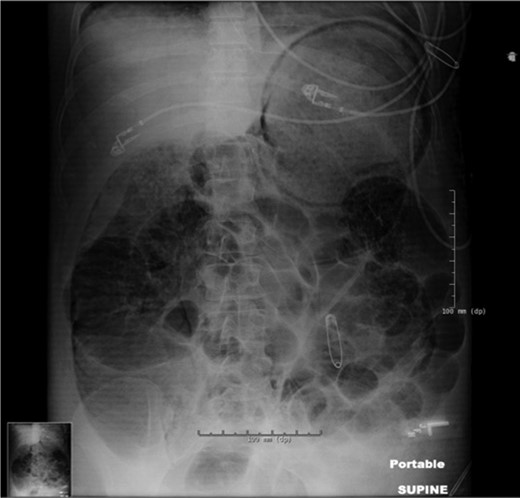

On the evening of post-burn day (PBD) 2, the patient developed a distended abdomen and became oliguric, unresponsive to volume challenge. A portable abdominal x-ray was concerning for pneumatosis of the stomach, small bowel and colon (Fig. 2). Computed tomography (CT) confirmed pneumatosis of the esophagus, stomach, small bowel and much of the colon, and hepatic portal venous gas (HPVG)—concerning for ischemic bowel (Fig. 3A–C) and prompting operative intervention. Of note, all vessels were patent. In the operating room (OR), the GI tract was distended with pneumatosis but without signs of ischemia except for a segment of mid-jejunum which was resected. She became hemodynamically unstable and thus left in discontinuity and an open abdomen.

Portable abdominal x-ray significant for pneumatosis of the stomach, small bowel and colon, without evidence of pneumoperitoneum. Note that safety pins visible in the image are external objects.